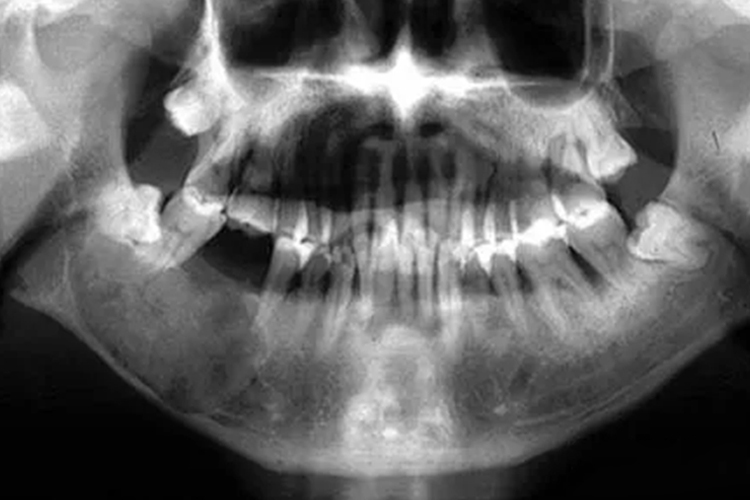

牙瘤多见于青年人,瘤体生长缓慢,早期无自觉症状。牙瘤发生部位可有骨质膨胀,可因肿瘤压迫神经出现神经疼痛,也可因拔牙或继发感染时才发现牙瘤存在。X线可见颌骨膨胀,有很多大小形状不一、类似发育不全的牙齿影像,或透射度似牙组织的一团影像,与正常骨组织之间有清晰阴影。